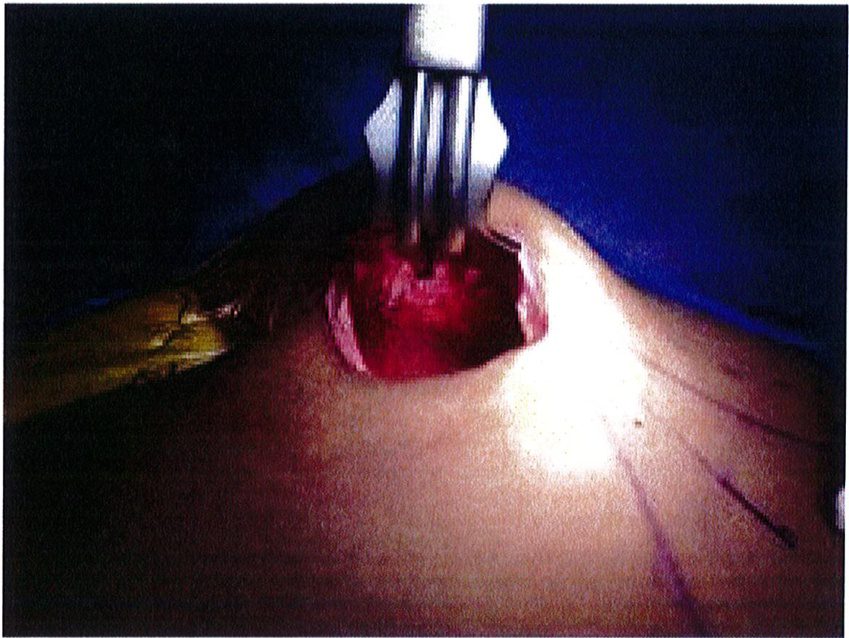

Dụng cụ bóc tách hai đầu tù, hình tròn được sử dụng để phân tách mặt phẳng vô mạch đã được bộc lộ bằng cách tiêm dung dịch trước đó, nhằm bảo tồn tối đa vách và lớp cân mạc. Nên thực hiện bóc tách từ trong ra ngoài, từ trên xuống dưới với một dụng cụ banh có đèn sợi quang (Hình 10). Để tách các vách ngăn, sử dụng một cây bóc tách dài có một đầu nhọn hoặc kéo dài (Hình 11). Các nhánh động mạch mông trên, mông dưới và một số mạch nuôi cho vùng cân mạc được đốt điện. Hãy chắc chắn

rằng cả hai bên túi được bóc tách trước khi đặt mô cấy để dễ dàng căn chỉnh hai bên cho cân đối (Hình 12 và 13). Sau khi bóc tách xong, sử dụng các sizer đặt vào mặt phẳng vừa bóc tách để xác nhận lại kích thước khối implant phù hợp cho bệnh nhân (Hình 14).